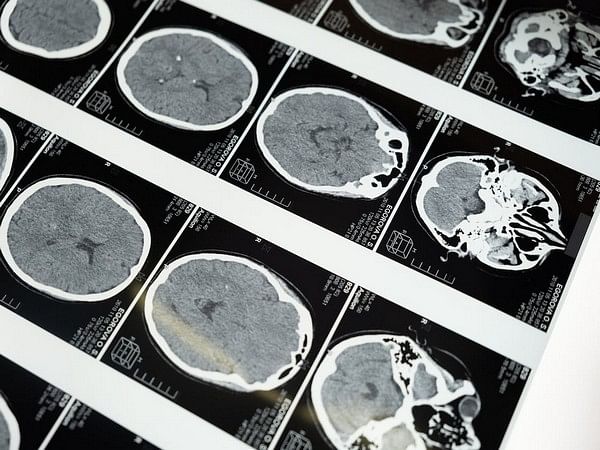

The loss of MYT1L led to electrophysiological hyperactivation in mouse and human neurons and thus impaired nerve function. Mice lacking MYT1L suffered from brain abnormalities, such as a thinner cerebral cortex. The animals also showed several ASS-typical behavioral changes such as social deficits or hyperactivity.